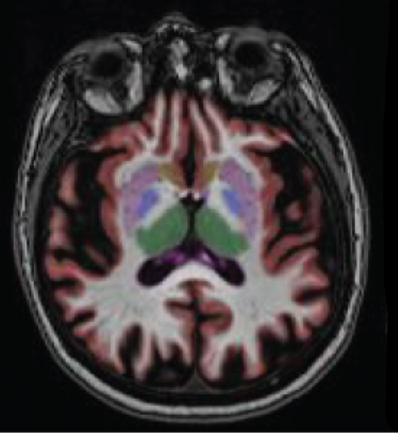

NEUROQUANT segmente et mesure le volume des hippocampes, des ventricules, des noyaux gris et de nombreuses autres structures cérébrales et compare le volume obtenu à celui d’une population de référence de même âge et de même sexe. Cette information permet une meilleure évaluation de l’impact de pathologies neurodégénératives ou neurologiques sur la morphologie du cerveau.

Pour le patient, un examen NEUROQUANT est une IRM cérébrale sans injection. L’examen nécessite une immobilité stricte du patient. Elle vient en complément d’un premier bilan visant à éliminer un diagnostic différentiel et est réalisée dans un second temps. Le manipulateur réalisant l’acquisition envoie les données sur un serveur sécurisé où NEUROQUANT identifie et segmente automatiquement les différentes structures cérébrales. Les valeurs de volume obtenues, par structure, sont comparées à une base de données de référence standardisée pour l’âge, le sexe et le volume cérébral. Le logiciel NEUROQUANT fournit plusieurs rapports permettant une évaluation visuelle et quantitative.